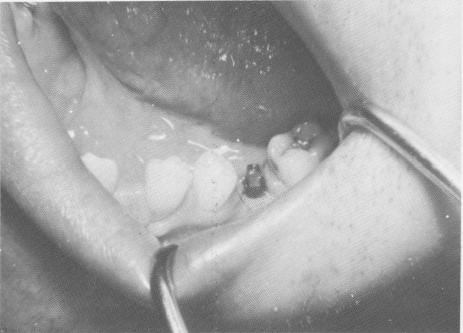

Fig. 8-5. The implant post should extend 3 or 4 mm. above the fibromucosal tissue and should not interfere with occlusion.

Fig. 8-4. With the use of a hand ratchet and a prolongator, the vent-plant is self-tapped into the underlying osseous structures.